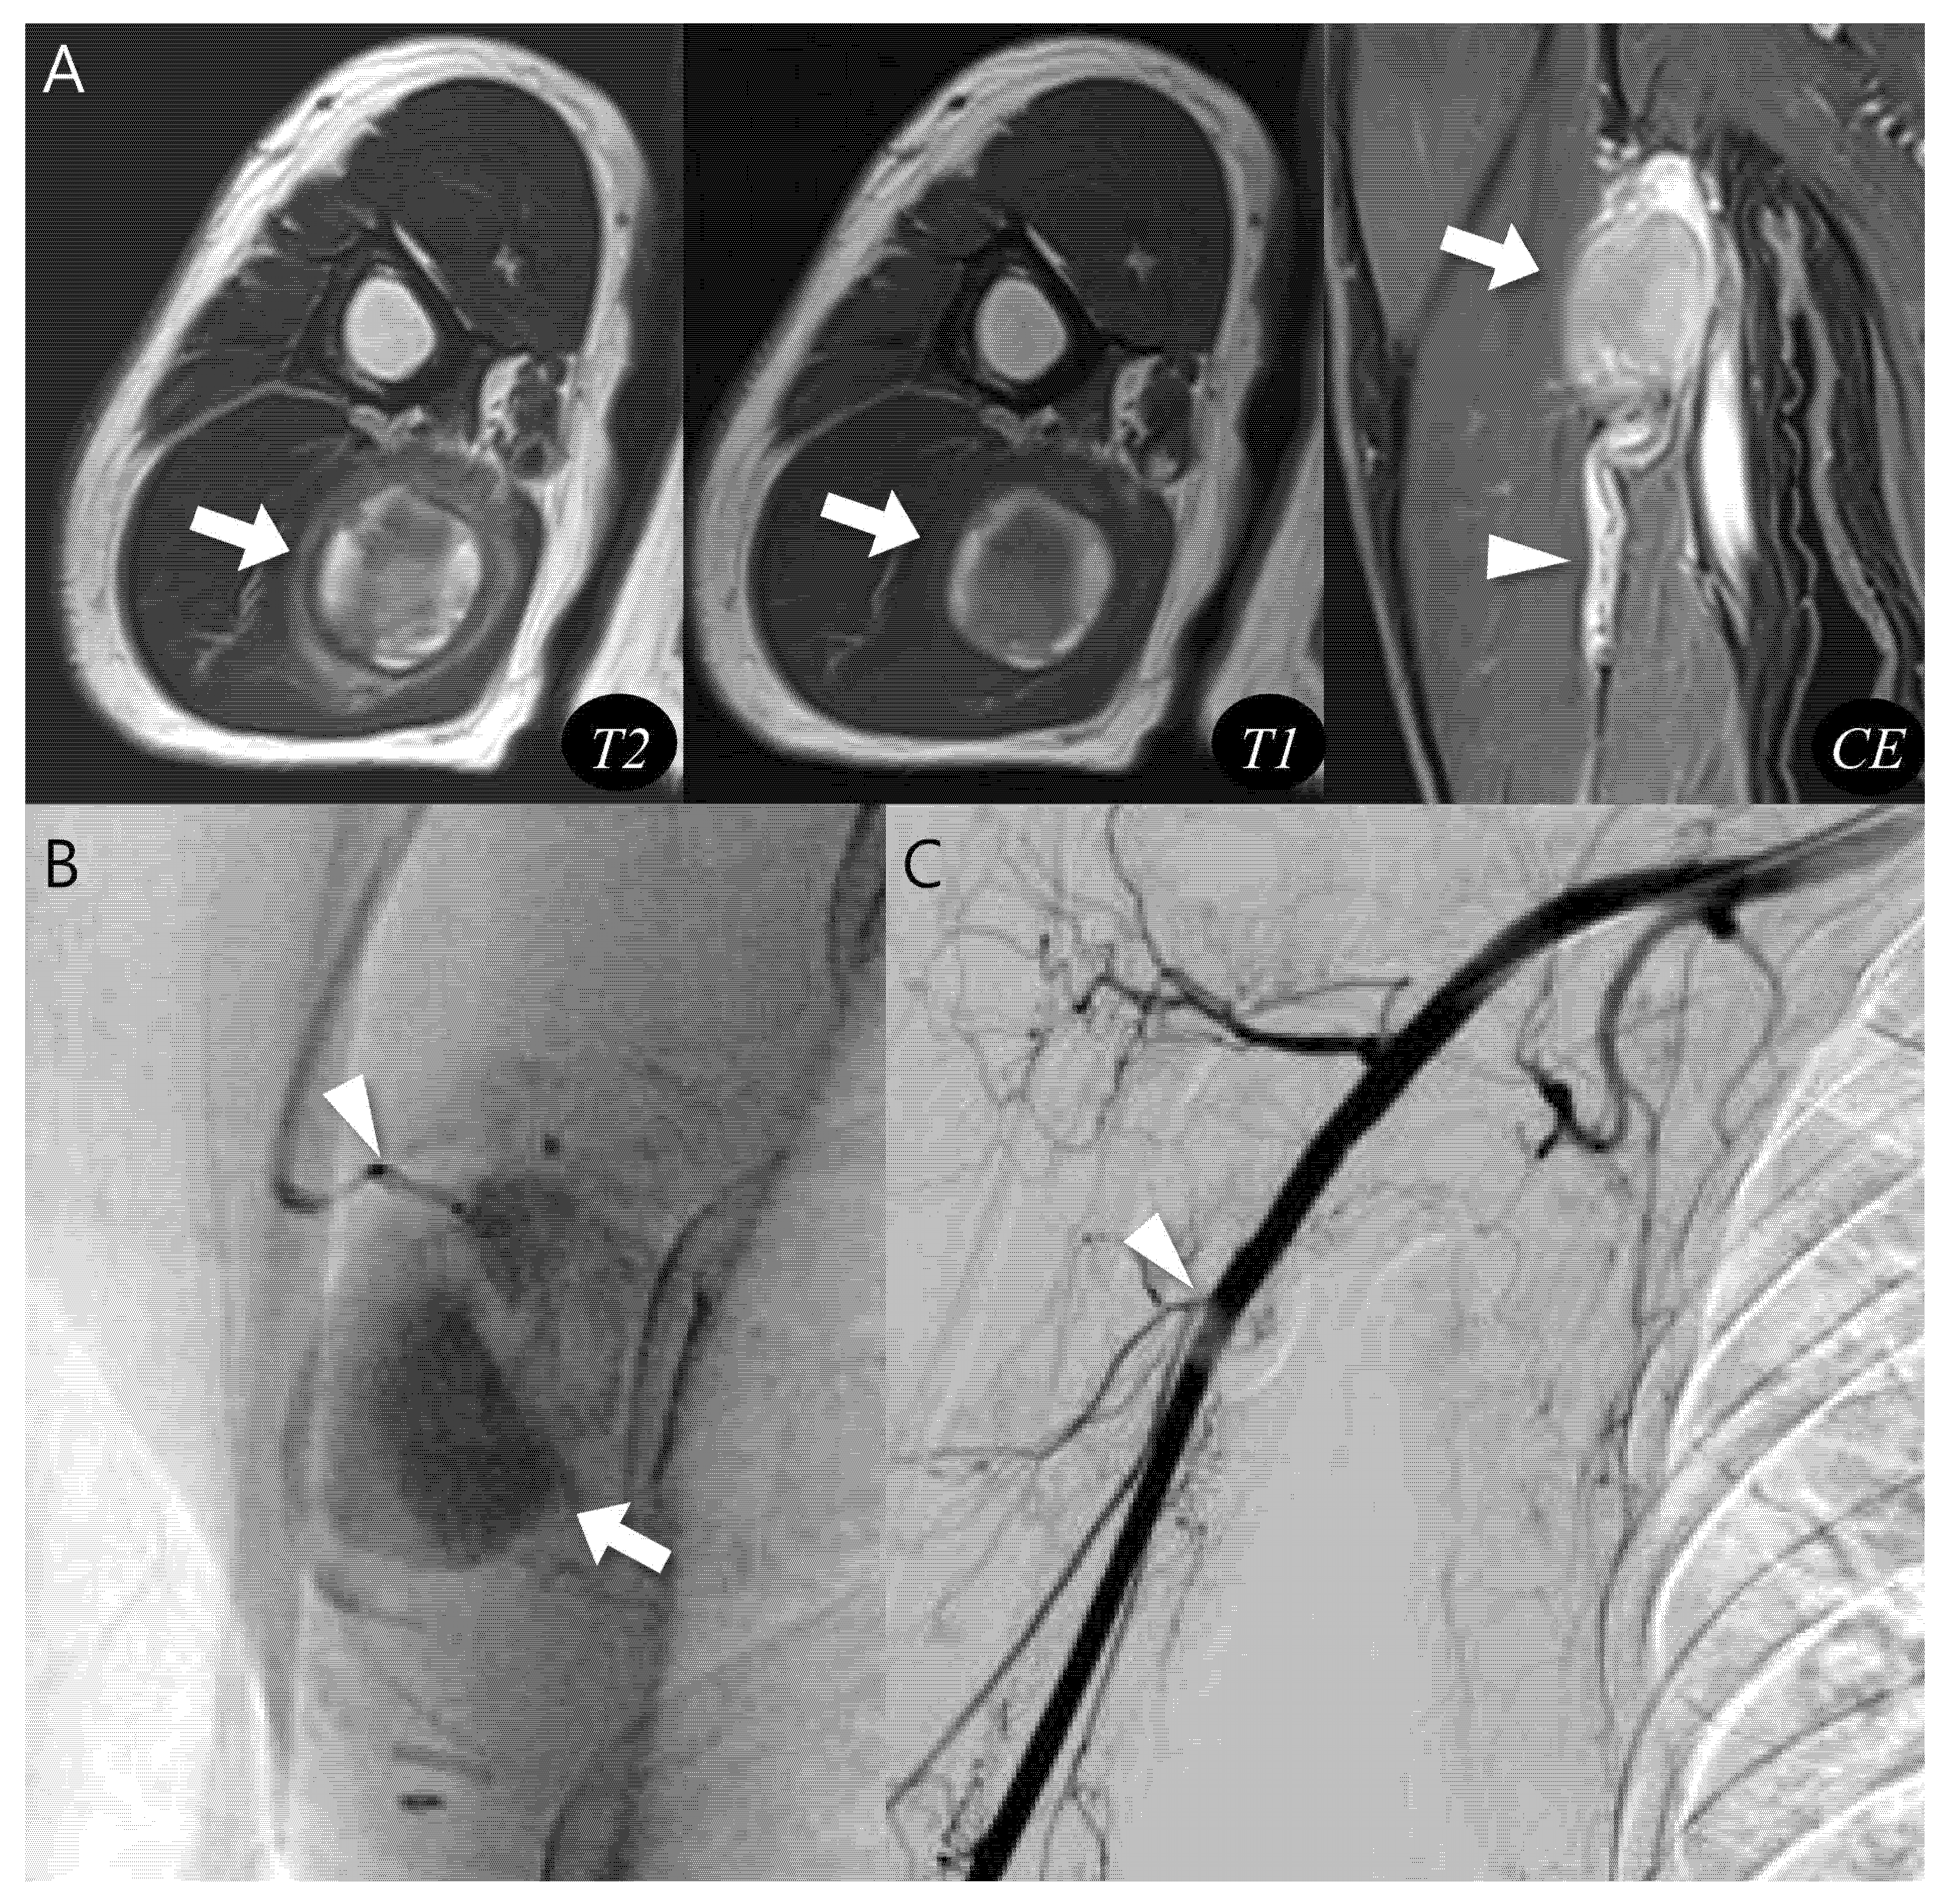

Using the proposed diagnostic flowchart, we successfully applied this approach in representative cases. In a representative pseudoaneurysm case (Figure 3), the hematoma-like lesion demonstrated a central flow void with adjacent neurovascular bundle involvement on MRI, which allowed a confident diagnosis of pseudoaneurysm; the patient subsequently underwent successful endovascular embolization. In contrast, in a CEH case (Figure 4), the lesion exhibited a multilobular hematoma-like lesion with internal septations and lacked neurovascular bundle involvement, findings that favored the diagnosis of CEH and were later confirmed after wide surgical excision. These representative cases underscore the practical utility of the flowchart by illustrating how specific imaging features can be translated into accurate diagnostic decisions and directly guide appropriate therapeutic strategies.

Figure 3.

Diagnosis and treatment of pseudoaneurysm. (A) Axial T2-weighted, T1-weighted, and coronal T1-weighted contrast-enhanced MR images show an intramuscular, ovoid lesions (arrow) in the upper arm. The lesion demonstrates a central flow void with inner peripheral high SI on T1-weighted image (arrow, mural thrombus) with neurovascular involvement (arrowhead). (B) Digital subtraction angiography reveals a pseudoaneurysm sac (arrow) with a narrow neck arising from the brachial artery (arrowhead). (C) Post-embolization angiography demonstrates successful occlusion of the pseudoaneurysm neck (arrowhead).